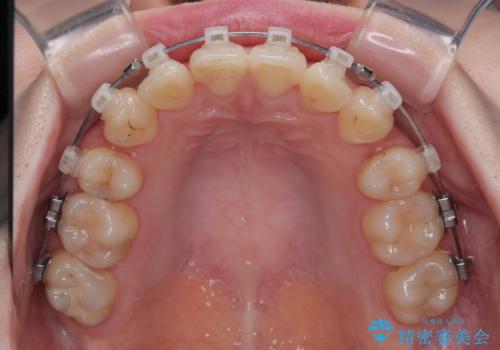

- クリアブラケット

上下ともに八重歯が顕著であり、前歯のクロスバイトがあったため、上下左右の第一小臼歯4本を抜歯し、ワイヤー装置での抜歯矯正を行うこととしました。

20歳ということもあり、歯の移動速度が非常に速く、1年強という短期間であっという間に治療を終えることができました。